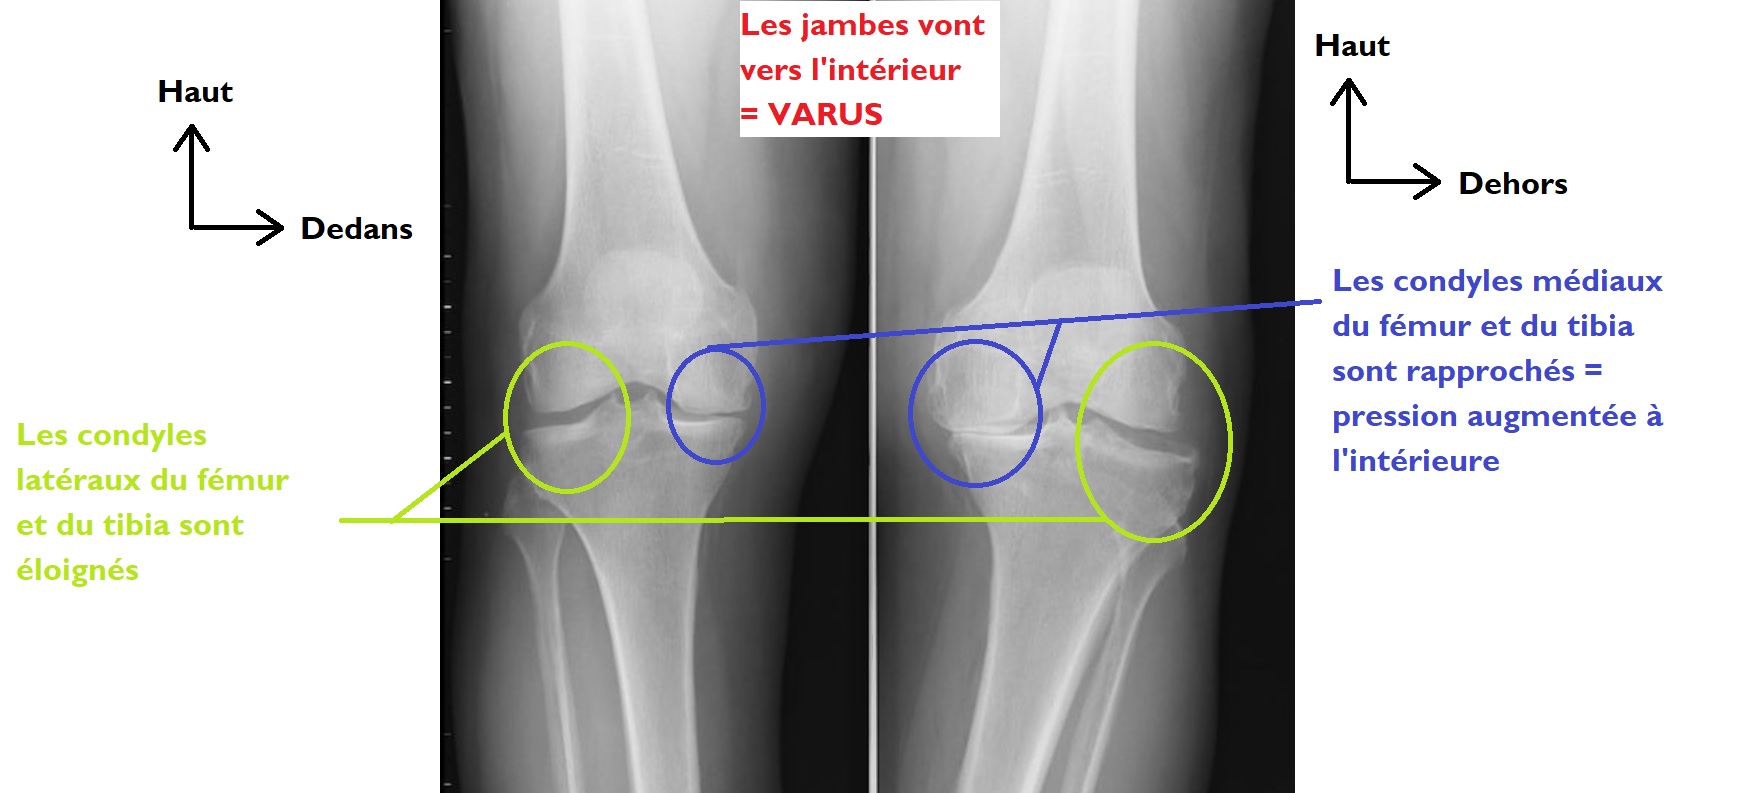

Si entre l’axe du fémur et l’axe de la jambe on a angle latéral / extérieur on parlera de valgus (genu valgum) = la jambe point vers l'extérieur

Si a l’inverse on a entre l'axe du fémur et de la jambe, un angle à l’intérieur / médialement, on aura un varus (genu varum) = la jambe pointe vers le dedans, l'intérieur, t'as les jambes arquées comme lucky luke.

C’est important car les condyles du fémur et du tibia s'articulent entre eux, et l'écart entre les condyles médiaux / latéraux du tibia et du fémur va changer selon qu'on a un valgus ou un varus :

- si on a un valgus, on écarte le condyle médial du fémur du condyle médial du tibia et on rapproche donc les condyles latéraux, ce qui cause une augmentation des pressions latéralement --> favorise l’arthrose fémoro-tibiale latérale.

- si on a un varus c’est l’inverse, on écarte les condyles latéraux du tibia et du fémur, on rapproche les condyles médiaux l'un de l'autre donc on augmente les pressions médialement --> favorise l'arthrose médiale

Radio d'un varus pour comprendre :

varus pressions.jpg